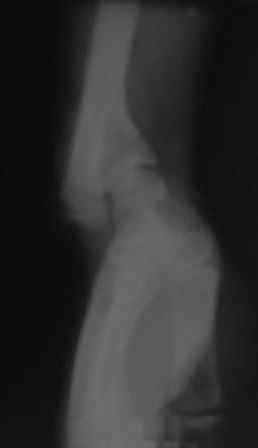

Доброго времени суток уважаемые коллеги! Обратился б-ной 16

лет.Травму получил 9 лет назад, перелом лучевой кости и надмышелковый

перелом плеча. Имеется деформация л/з сустава типа лучевой

косорукости, укорочение п/плечья, отсутствия локтевой девиации,

cubitus varus под углом 25гр. Просит первоначально исправить

деформацию л/з сустава и восстановить длину п/плечья. Наш план-

остеотомия дистального метафиза лучевой кости, коррекция деформации и

удлинение по методу Илизарова. Уважаемые коллеги, помогите советом!

Может быть, есть какие-то нюансы , или другие методы? Снимки

прилагаются.